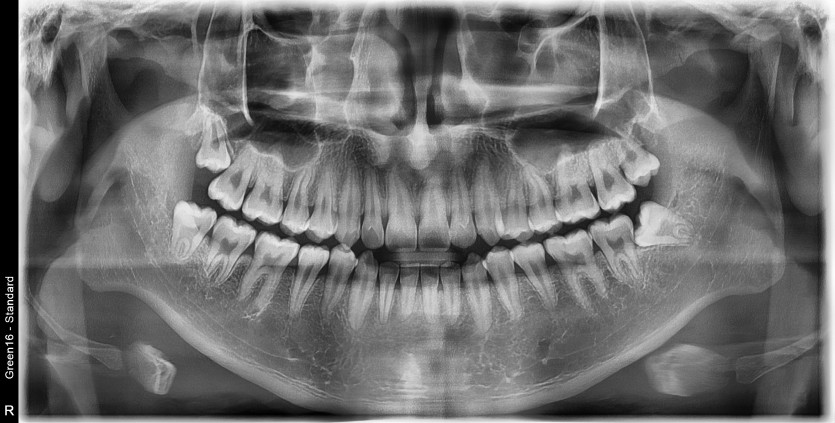

#18,28,38,48 사랑니 발치

구강 외과 전문의가 당일 발치했습니다.